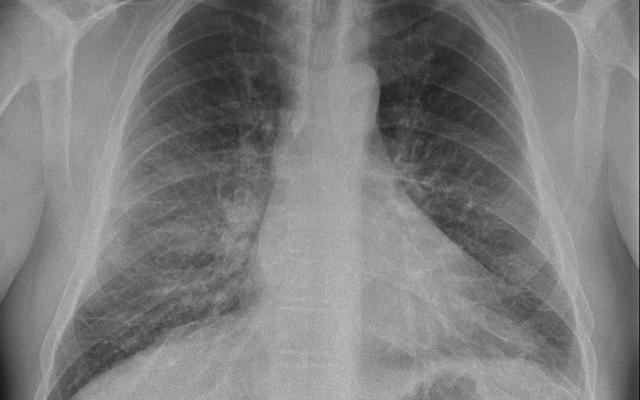

Een 64-jarige man met een blanco voorgeschiedenis kwam op de SEH vanwege plots ontstane dyspneu tijdens duiken in een veenmeer. Na ongeveer 30 minuten duiken bemerkte hij meer behoefte aan perslucht, waarna hij direct zijn duik had beëindigd. Bij lichamelijk onderzoek zagen wij een dyspnoïsche patiënt met duidelijke crepitaties bibasaal. Zijn saturatie was 90% bij kamerlucht. Voorts was hij hypertensief met een bloeddruk van 173/97 mmHg. Het ecg was niet afwijkend. Bloedgasanalyse liet met een pO2 van 9,2 kPa een geïsoleerde hypoxemie zien. Op de X-thorax zagen wij Kerley-B-lijnen en versterkte tekening van de pulmonale vaten. Bij echografie was…